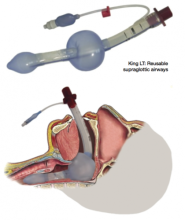

The second image shows the so called supraglottic airway device. The latest design is penis shaped:

But there are others: